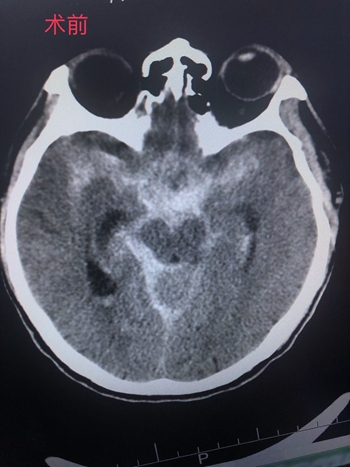

急急急!颅内动脉瘤破裂出血致呼吸停止,我院神经外科团队成功救治危重患者

近日,我院神经外科团队成功救治一名颅内动脉瘤破裂出血致呼吸停止患者,目前患者生命体征平稳,已康复出院。该病例的成功救治,标志着我院卒中中心绿色通道的成熟打造,介入科拥有处理高难度介入手术的能力。彰显我院综合实力的不断提高。

深夜“爆血管”,上演死神来袭

某日凌晨,外院紧急转送一名神志不清患者到我院急诊科,经体查患者入院时神志嗜睡,颈抵抗明显,伴有脑膜刺激征,外院CT提示蛛网膜下腔出血......首诊医生林雨杭研判,患者高度疑似颅内动脉瘤破裂出血,“时间就是大脑”情况十分紧急,在跟患者家属解释病人病情危重、急需手术等情况的同时启动卒中中心绿色通道,直达手术室。

(术前CT)                                                                  (术后CT)